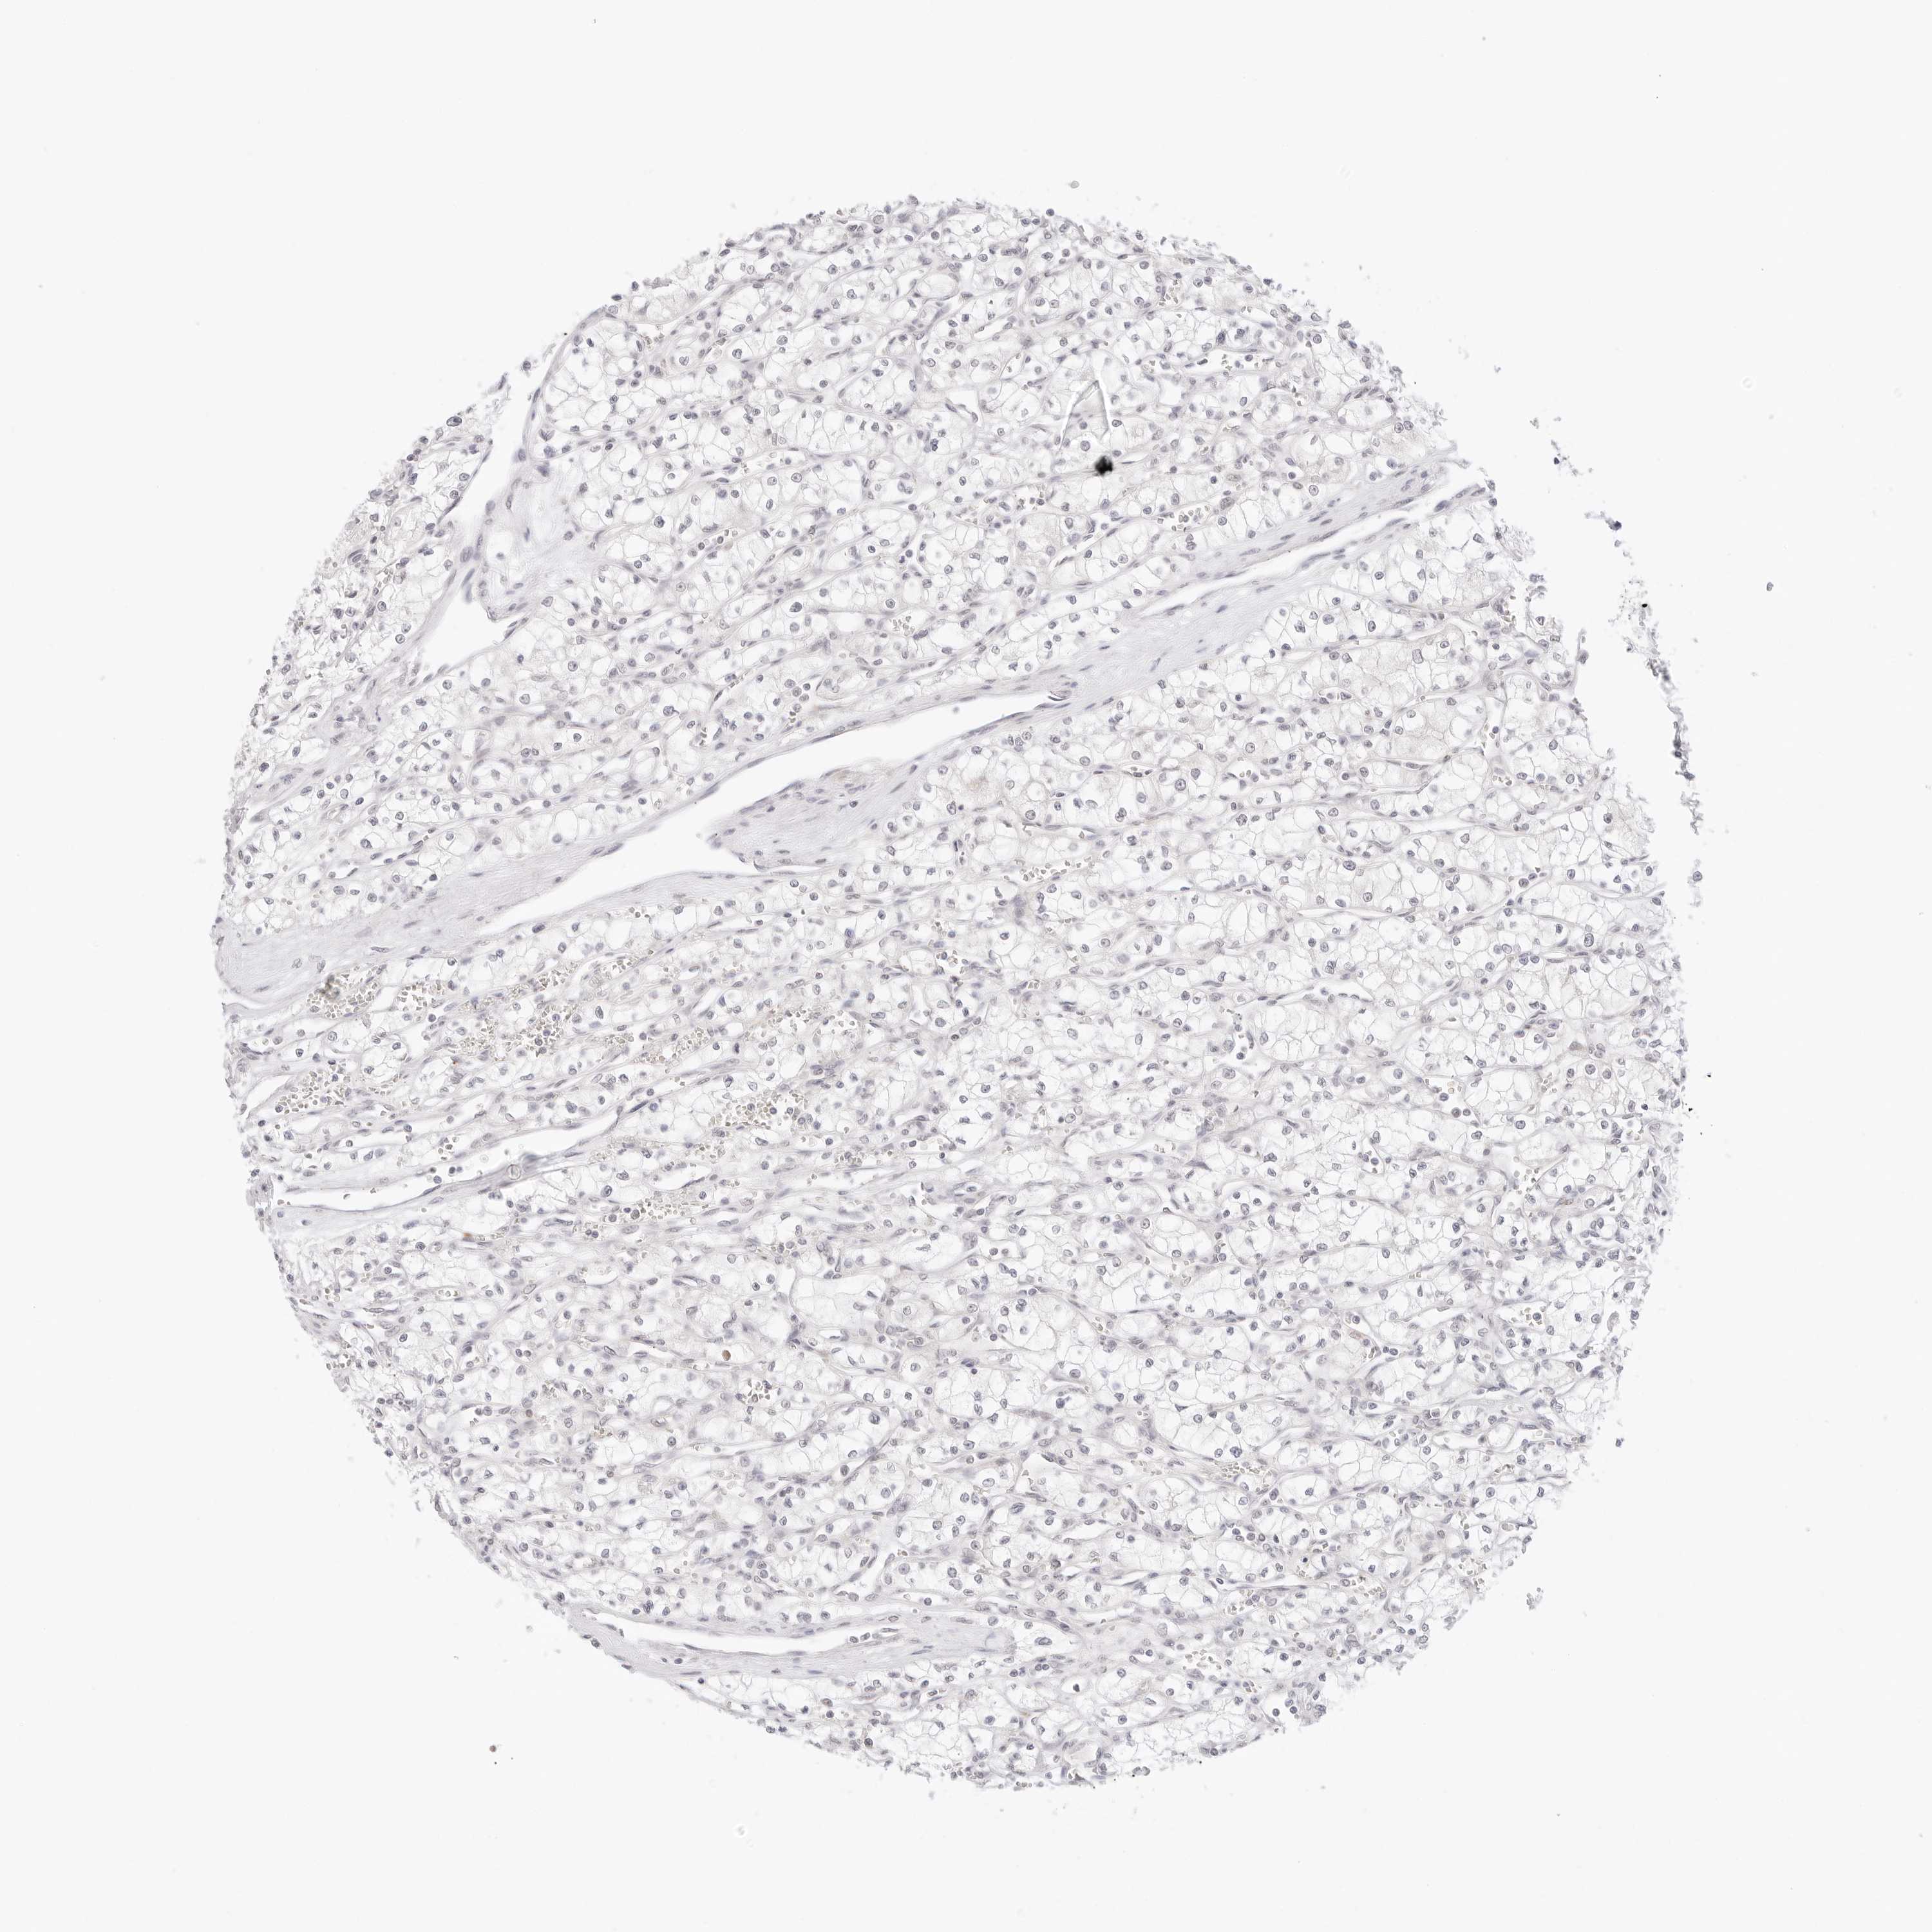

KIDNEY RENAL PAPILLARY CELL CARCINOMA (TCGA) - Interactive survival scatter ploti

The Survival Scatter plot shows the clinical status (i.e. dead or alive) for all individuals in the patient cohort, based on the same data that underlies the corresponding Kaplan-Meier plots. Patients that are alive at last time for follow-up are shown in blue and patients who have died during the study are shown in red.

The x-axis shows the expression levels (FPKM) of the investigated gene in the tumor tissue at the time of diagnosis. The y-axis shows the follow-up time after diagnosis (years). Both axes are complimented with kernel density curves demonstrating the data density over the axes. The top density plot shows the expression levels (FPKM) distribution among dead (red) and alive patients (blue). The right density plot shows the data density of the survived years of dead patients with high and low expression levels respectively, stratified using the cutoff indicated by the vertical dashed line through the Survival Scatter plot. This cutoff is automatically defined based on the FPKM cutoff that minimizes the p-score. The cutoff can be changed by dragging the vertical line or by entering a cutoff value in the square labeled "Current cut-off".

Under the Survival Scatter plot the p-score landscape (black curve; left axis) is shown together with dead median separation (red curve; right axis). Dead median separation is the difference in median mRNA expression between patients who have died with high and low expression, respectively. It is calculated as follows: median FPKM expression of dead patients with high expression - median FPKM expression of dead patients with low expression. This is intended to aid the user in visually exploring custom cutoffs and the associated p-scores and dead median separation.

Individual patient data is displayed and can be filtered by clicking on one or more of the category buttons on the top of the page. Categories describing expression level and patient information include: high, low, alive, dead, female, male and tumor stages. The scale of the x-axis can be toggled between linear and log-scale by clicking on the "x log" button. Mouse-over function shows TCGA ID, patient information and mRNA expression (FPKM) for each patient.

& Survival analysisi

Kaplan-Meier plots summarize results from analysis of correlation between mRNA expression level and patient survival. Patients were divided based on level of expression into one of the two groups "low" (under cut off) or "high" (over cut off). X-axis shows time for survival (years) and y-axis shows the probability of survival, where 1.0 corresponds to 100 percent.

XKR4 is not prognostic in Kidney Renal Papillary Cell Carcinoma (TCGA)